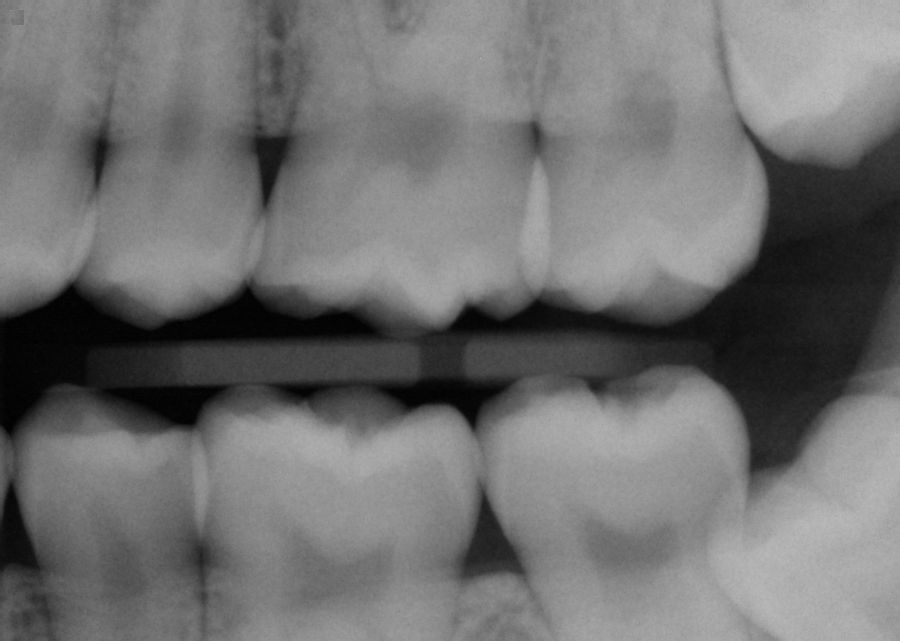

Bitewing dental xrays News Dentagama